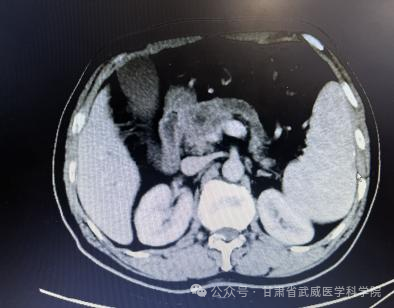

胰腺癌一经确诊没有手术根治机会平均生存期在三个月到半年左右,部分患者能够手术根治切除,术后总体五年生存率不超过5%。本病发病率男性高于女性,男女之比为1.5~2:1,男性患者远较绝经前的妇女多见,绝经后妇女的发病率与男性相仿。胰腺癌诊治困难主要在于其起病隐匿、转移迅速。武威肿瘤医院腹部外科凭借强大的技术力量,近日连续治疗了肝门胆管癌,胰腺癌等数例高难度患者,手术均成功实施,且患者均恢复顺利出院,我科2023年02月收治一例胰头部占位,经科主任仔细阅片、全科讨论后患者胰腺癌肿瘤侵犯门静脉(环周超过1800)及胃十二指肠动脉无外科切除机会,经过术前五周期全身静脉化疗(吉西他滨1000㎎/m2+白蛋白结合型紫杉醇125㎎/m2 D1、8)后CT评估该患者胰腺癌瘤体明显缩小,肿瘤与门静脉主干、胃十二指肠动脉之间有了一定的间隙,与患者家属积极交代病情及沟通后于2023-7-为该患者施行“根治性胰十二指肠切除+I125粒子植入术”,现恢复良好,总生存时间已超过1年。

经过5周期化疗后复查腹部CT资料